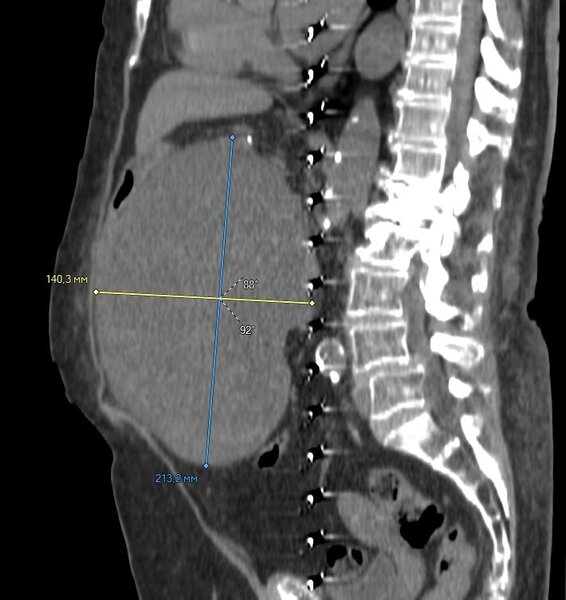

Ультразвуковое исследование подтвердило опасения, выявив крупное новообразование в брюшной полости. Особую тревогу врачей вызывала его динамика — опухоль продолжала стремительно расти. После прохождения всех необходимых дополнительных обследований пациентка была направлена на консультацию к хирургам Красноярской городской больницы №20.

«Ситуация была критической, — пояснил хирург Сергей Александрович Борисов. — Опухоль достигла таких размеров, что оказывала сильное давление на магистральные кровеносные сосуды и протоки в брюшной полости. Это не только вызывало сильные боли, но и создавало прямую угрозу жизни: пациентке было тяжело принимать пищу, нарастали риски развития тромбоза, острой кишечной непроходимости и полиорганной недостаточности».